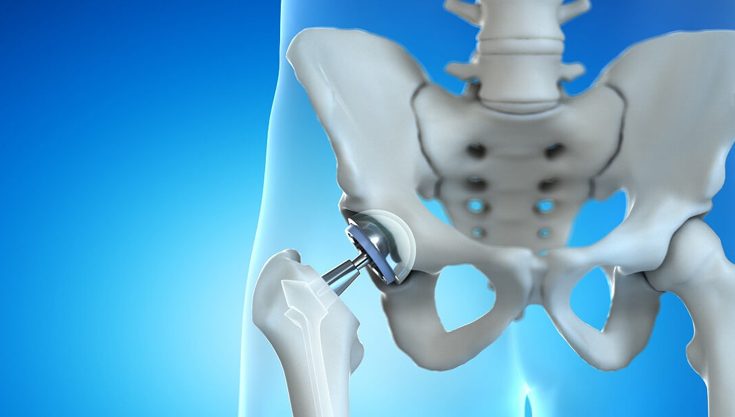

Dr. Vijay Kumar Sohanlal is an esteemed orthopedic surgeon, specializing in joint replacement. Renowned for his expertise in robotic knee replacement , Total knee & hip replacement , revision knee & revision hip replacement, he has helped numerous patients regain mobility and improve their quality of life. He has trained extensively under some of the world’s leading orthopaedic specialists across Australia, Germany, and Mumbai. Dr. Sohanlal’s skills enable him to perform bilateral knee joint replacements in a single sitting, minimizing recovery time and hospital stays for his patients.